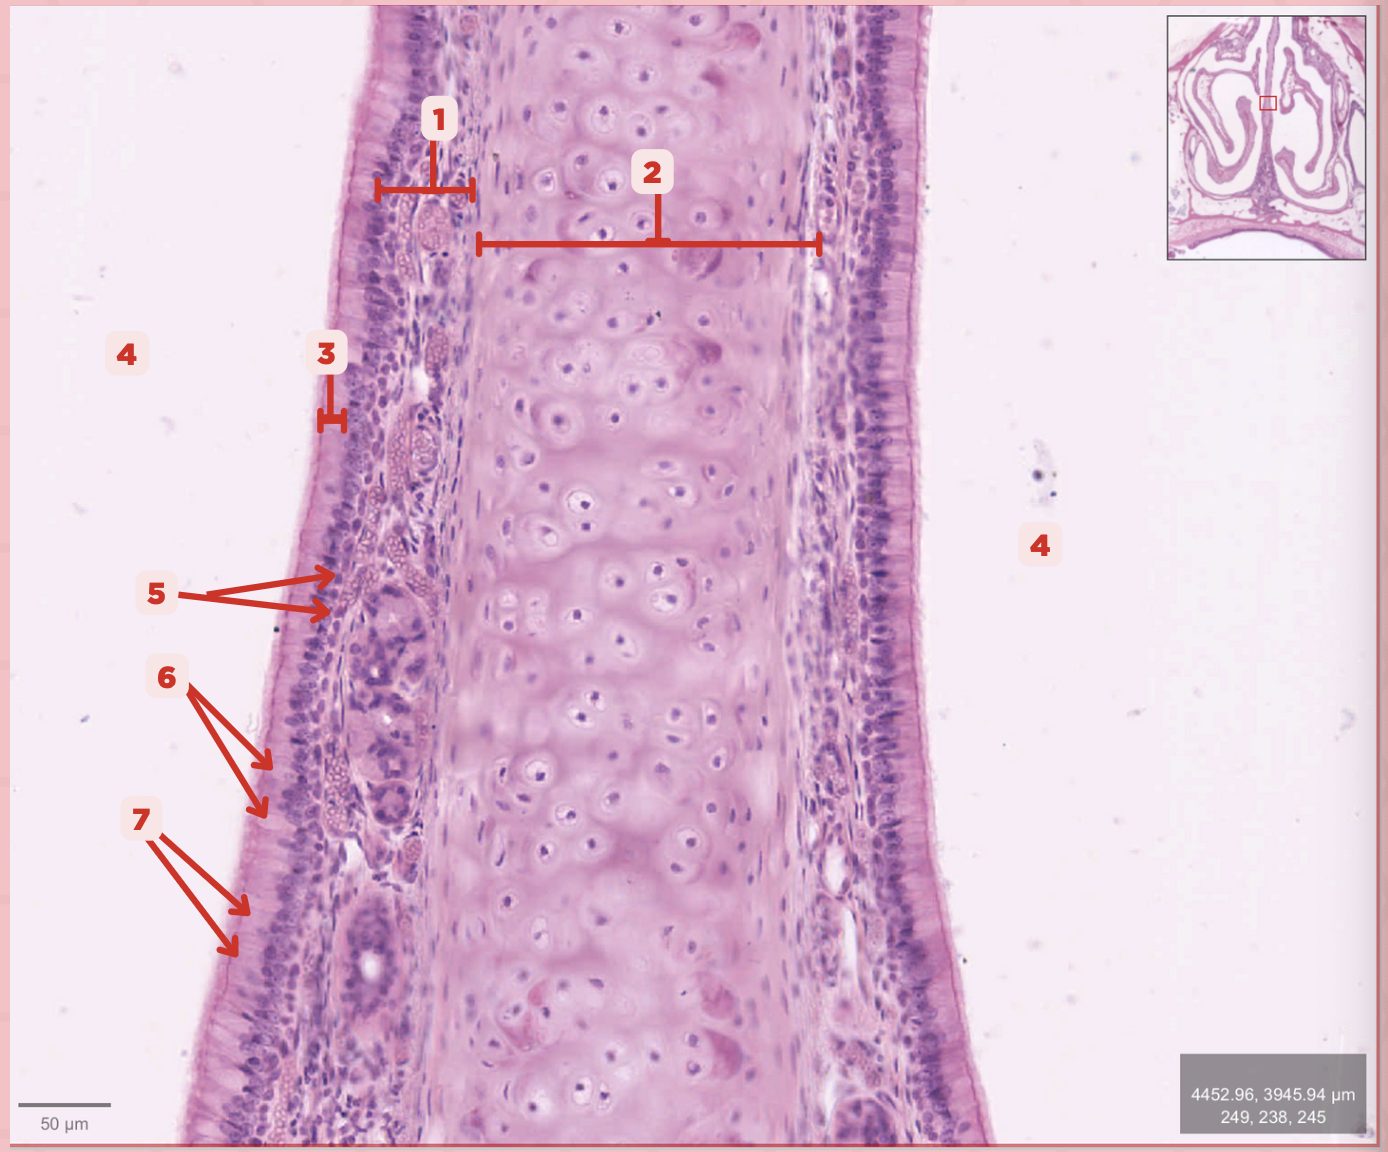

Identify the structure labeled as 1.

Hyaline Cartilage

Identify the structure labeled as 2.

Respiratory Epithelium

Identify the structure labeled as 3.

Nasal Cavity

Identify the structure labeled as 4.

Basal Cells

Identify the structure labeled as 5.

Goblet Cells

Identify the structure labeled as 6.

Ciliated Columnar Cells

Identify the structure labeled as 7.

Adipose tissue

What type of tissue is sometimes seen between the bony spicules?

Serous and Mucous Glands

What glands are present in the Lamina Propria?